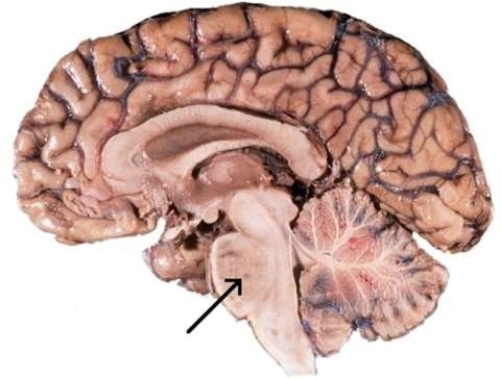

What is the function of the region of the brain referred to in this image?

A) It connects parts of the brain with one another by means of tracts, and influences respiration.

B) It is responsible for precise control of muscle movements, maintenance of posture, and maintaining balance.

C) It is involved in the regulation of heart rate, blood vessel diameter, coughing and swallowing.

D) It connects the cerebellum with the cerebrum, and acts a relay for auditory and visual impulses.

It connects parts of the brain with one another by means of tracts, and influences respiration.